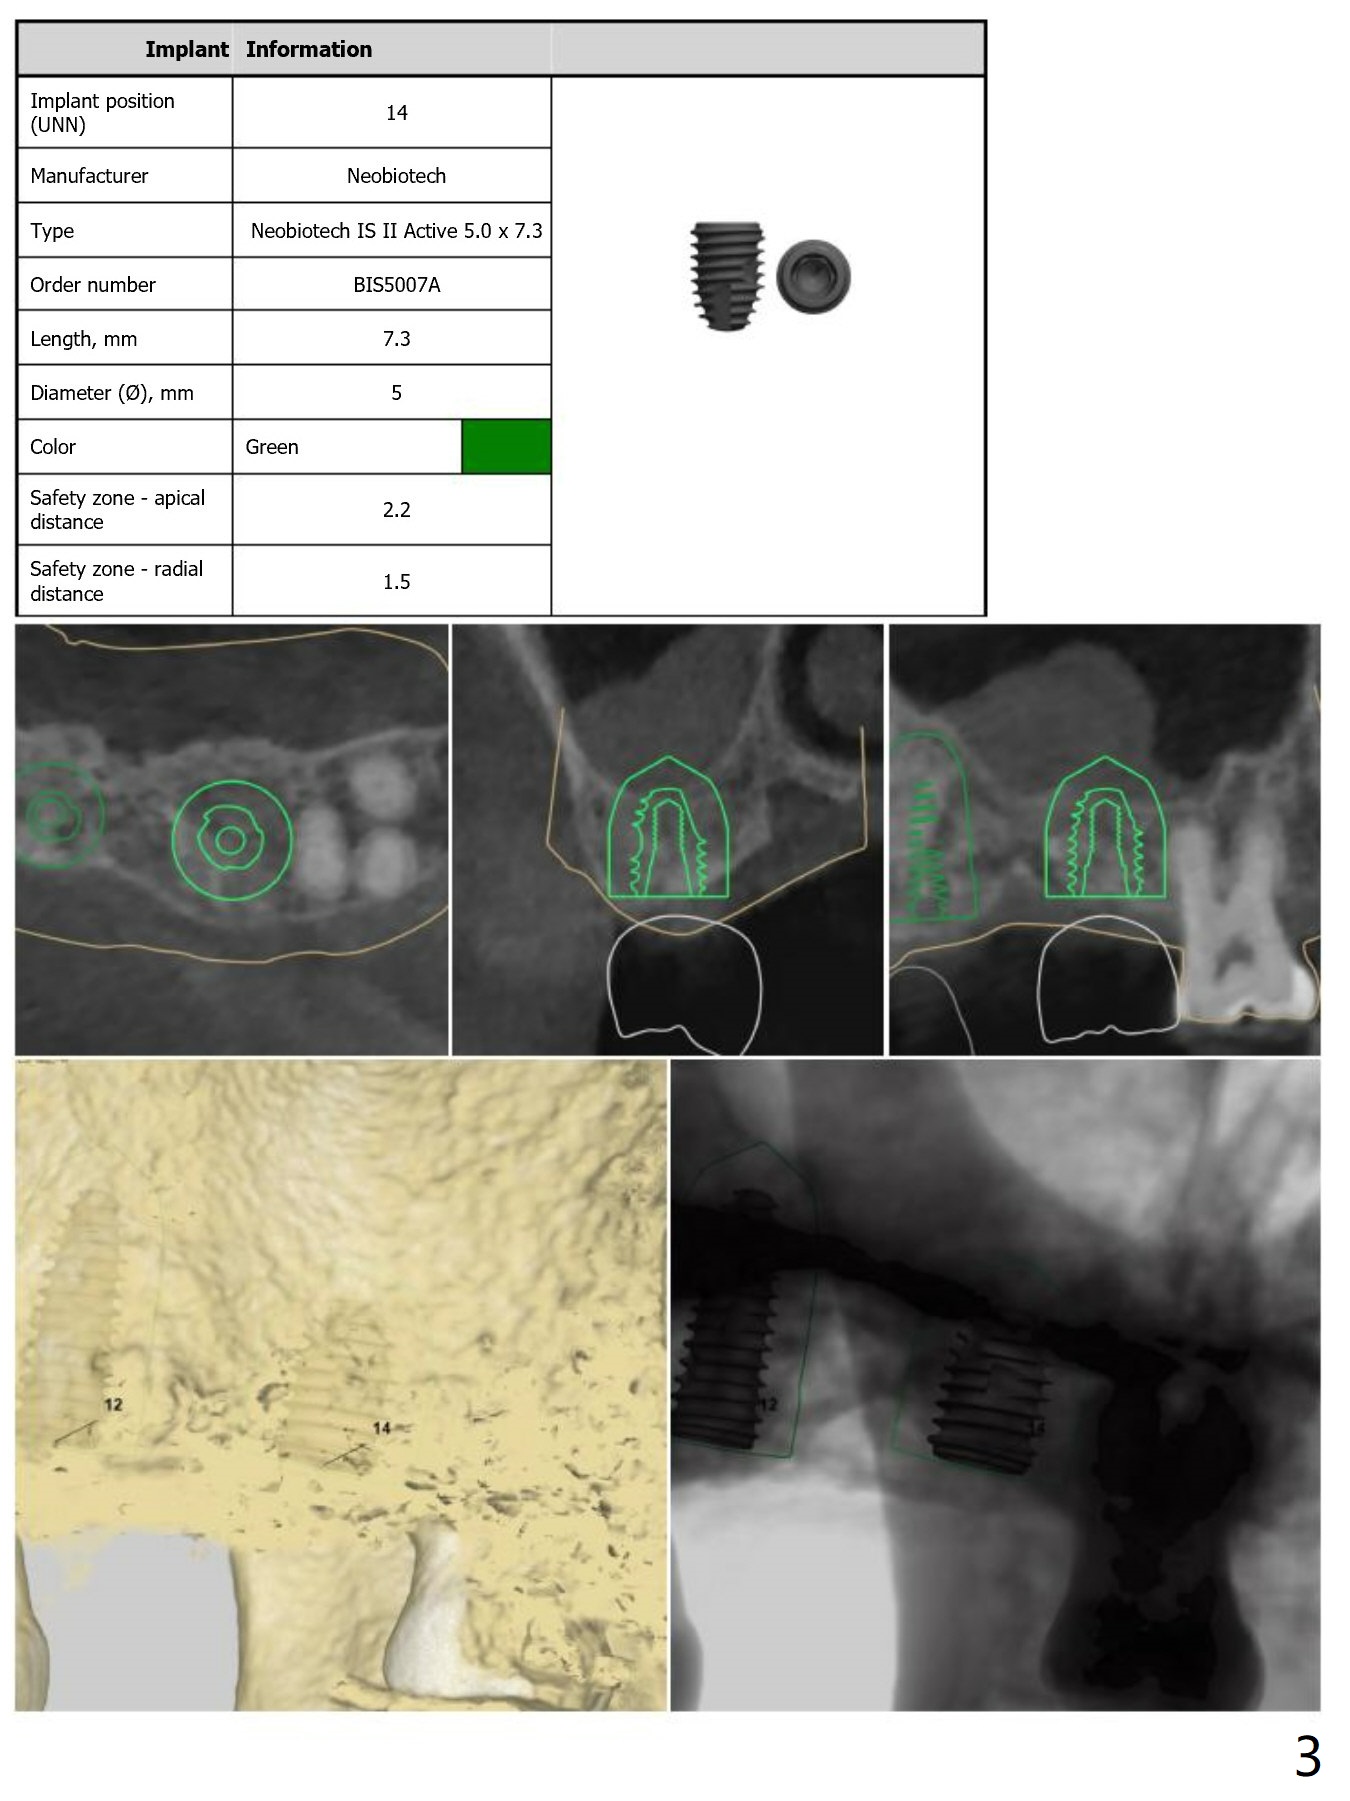

Return to Upper Molar Immediate Implant, Armaments